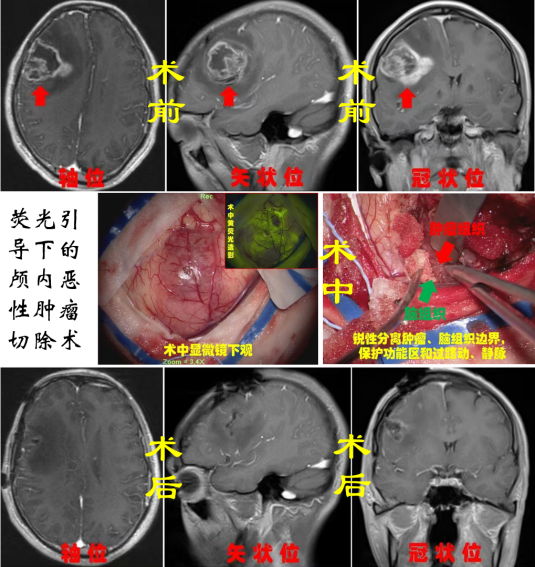

神經(jīng)腫瘤:神經(jīng)腫瘤作為神經(jīng)系統(tǒng)疾病中最為棘手的疾病之一,常見的有膠質瘤、腦膜瘤、垂體瘤、神經(jīng)鞘瘤、轉移瘤、先天性腫瘤等,手術方式包括超聲導航+熒光造影引導下腦腫瘤切除術、鞍結節(jié)腦膜瘤切除術等,借助顯微鏡等先進設備,在保留正常腦組織的情況下,最大程度切除腫瘤組織,為患者爭取后續(xù)康復機會。